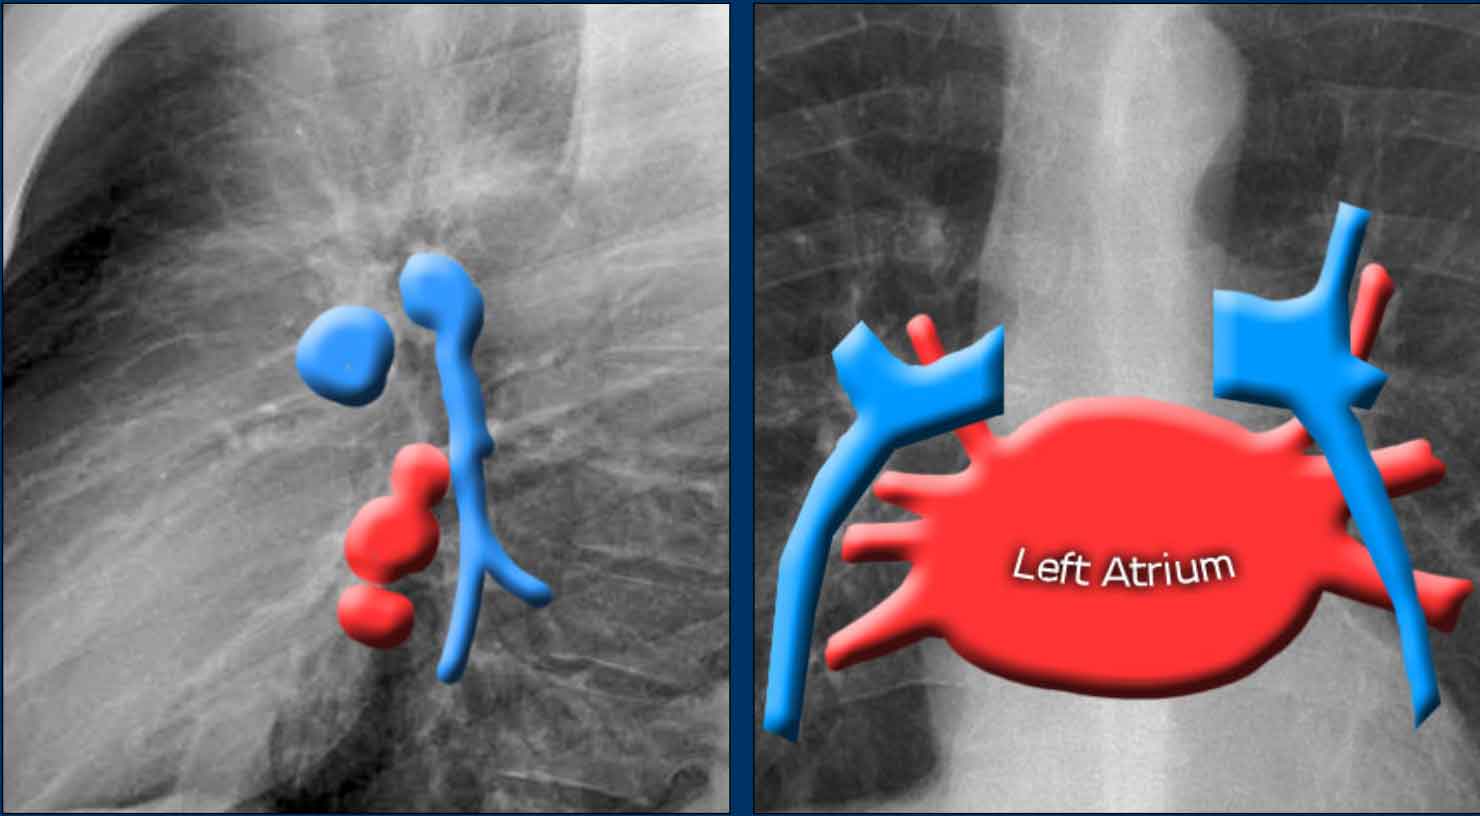

Left Atrium (LA)

It is the most posterior cardiac chamber and it receives oxygenated blood from the pulmonary veins, which enter the left atrium almost horizontally. The left atrial appendage is occasionally visible as a small outpouching just below the pulmonary trunk (best seen on lateral view).

Radiographic signs of left atrial enlargement:

• PA view: Bulging of the upper right heart border and widening of the carinal angle due to splaying of the main bronchi.

• Lateral view: Bulging of the posterior-superior cardiac contour.

In this illustration, lower lobe pulmonary arteries are colored blue to indicate deoxygenated blood.

These arteries have a more vertical orientation compared to the pulmonary veins, which run more horizontally toward the left atrium, located inferior to the level of the main pulmonary arteries.

The left main pulmonary artery passes superior to the left main bronchus and lies higher than the right pulmonary artery, which courses anterior to the right main bronchus.